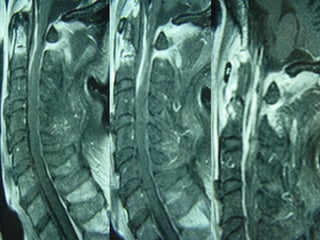

Magnetic resonance imaging

lumbosacral spine showing a

T1W isointense lesion

intradural extramedullary

lesion at D12-L1 level

measuring about 11.4 × 11.2

× 22.8 mm displacing the

conus and cauda (a and b).

On contrast (c and d) there is

heterogenous enhancement

with hypointense center and

peripheral enhancement